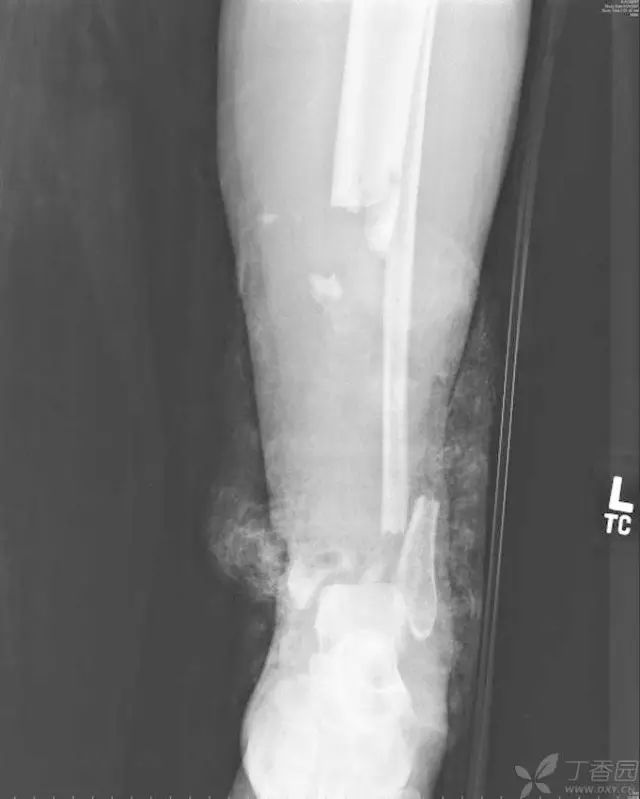

2-5 年 X 线片,可见距下关节、胫距关节关节炎。距骨体逐渐出现硬化,无塌陷

33 岁男性,车祸多发伤。左踝严重污染,几乎环形创口,胫骨远端 20 cm 缺损

游离骨块生理盐水灌洗,保持湿润,4 小时内紧急手术。术中对创口和游离骨块各用 12L 生理盐水灌洗,彻底清创。外固定支架固定,创口松散地缝合

原计划 48 小时再次灌洗,因身体情况不稳定,10 天后再次进手术室清创灌洗,方法如前;48 小时后进行了第三次灌洗,然后进行了内固定,闭合创口。

3 个月后创口无感染迹象,骨折处无压痛

6 个月后,骨折线模糊,独立行走

18 个月恢复工作